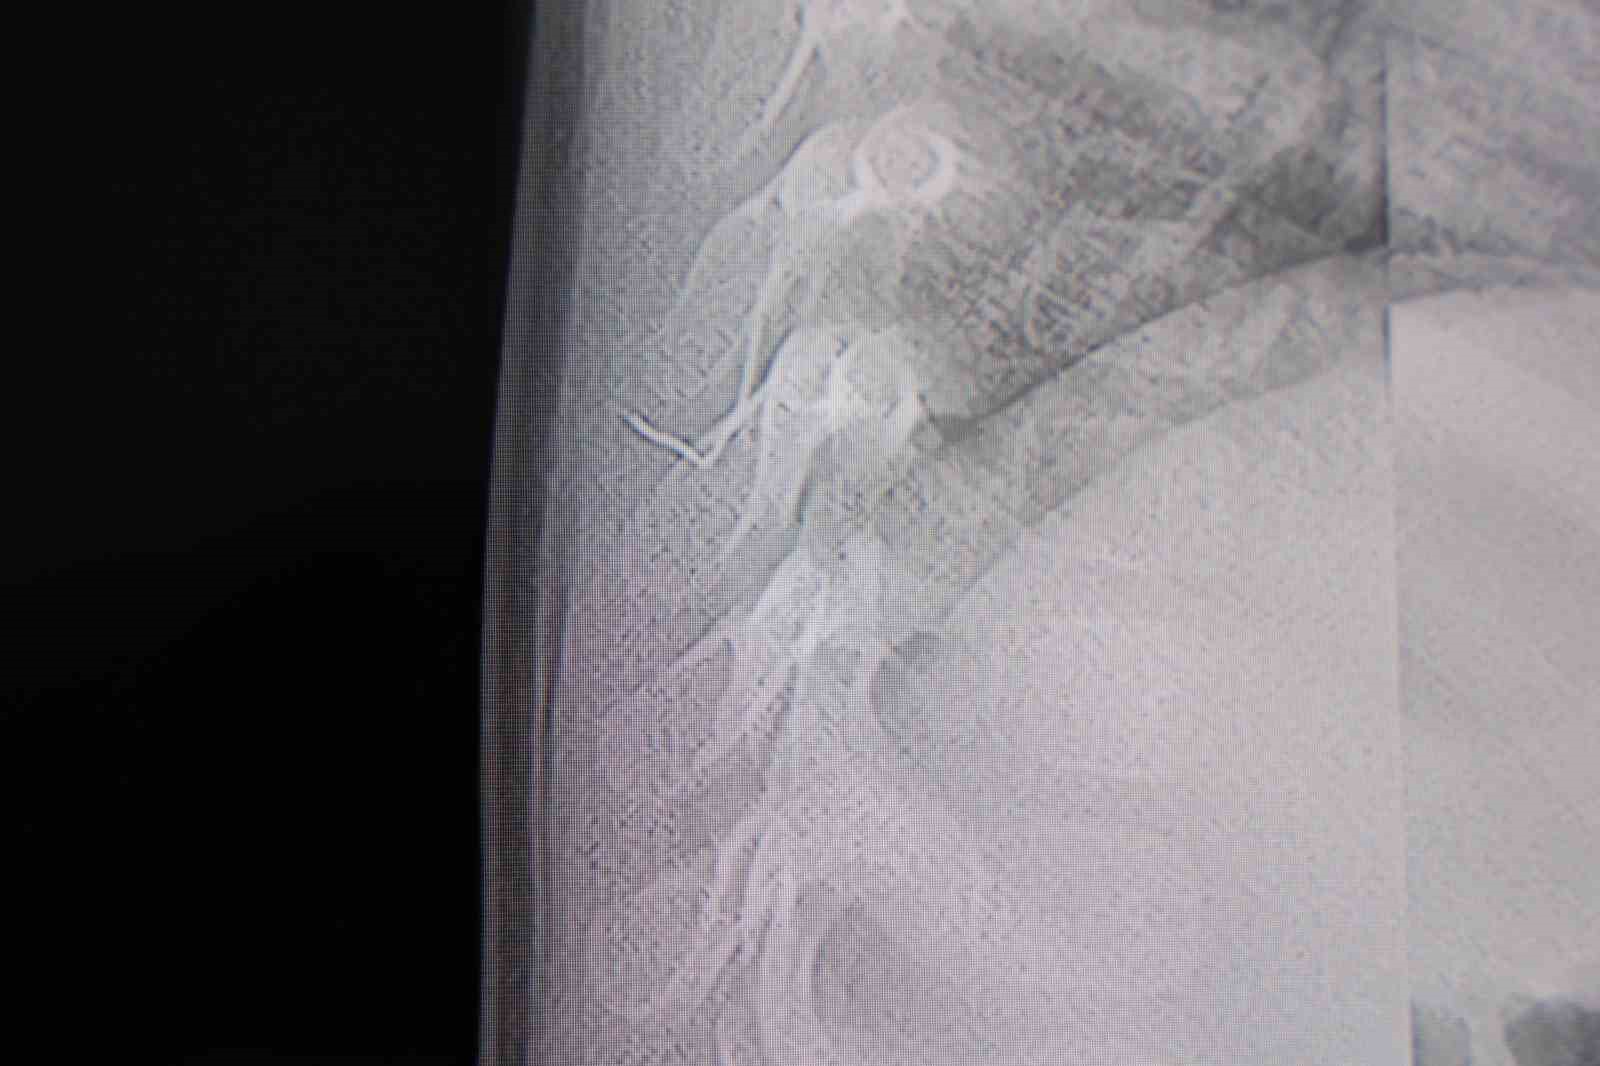

Alınan bilgiye göre, Kahramanmaraş’ta farklı ortopedi, çocuk cerrahisi ve beyin cerrahisi kliniklerine başvurusu yapılan bir yaşındaki bebeğin, sırt bölgesinde yabancı bir cisim olduğu ancak müdahalenin zor olduğu ve 8 yaşına kadar beklenmesi gerektiği bildirildi. Aile, bebekleri için son olarak HG Hospital’e başvurdu. HG Hospital Beyin ve Sinir Cerrahisi Uzmanı Prof. Dr. İdris Altun tarafından yapılan tetkiklerde, yabancı cismin cilt altında, omurilik kanalına yakın bir bölgede olduğu ve akciğer zarına doğru ilerlediği belirlendi. Hasta, genel anesteziye alınmadan, lokal anestezi ve sedasyon eşliğinde ameliyata alındı. Yapılan müdahalede yabancı cisim tamamen çıkarıldı. Çıkarılan cismin, ince zımba teline benzer metal bir tel olduğu ve yaklaşık 2 santimetre uzunluğunda bulunduğu tespit edildi. Hasta, aynı gün taburcu edildi.

Konuya ilişkin açıklama yapan Prof. Dr. İdris Altun, "Sırtında yabancı bir cisim olduğu söylenmiş ancak çıkarılamayacağı ve 8 yaşına kadar beklenmesi gerektiği ifade edilmişti. Bize başvurduğunda yaptığımız tetkiklerde, cilt altında, omurilik kanalına çok yakın ve akciğer zarına doğru ilerleyen bir yabancı cisim tespit ettik. Hastamızı tamamen uyutmadan, lokal anestezi ve sedasyon eşliğinde müdahale ederek lezyonu tamamen çıkardık. Çıkardığımız cismin ince zımba teline benzer, yaklaşık 2 santimetre uzunluğunda metal bir tel olduğunu gördük. Bu yabancı cisim alınmasaydı, bölgede enfeksiyon gelişebilirdi. Enfeksiyon sonucu omurilik kanalında ciddi hasarlar oluşabilir, çocuk büyüdükçe cismin hareket etmesine bağlı olarak omurilikte zedelenmeler meydana gelebilirdi. Ayrıca yana doğru ilerleyerek akciğer zarına ve akciğere batma riski vardı. Bu da enfeksiyona ve ilerleyen süreçte tümörle karışabilecek tablolara neden olabilirdi. Şu an hastamız gayet sağlıklı. Gerekli kontrolleri yaptık ve aynı gün taburcu ettik" dedi.